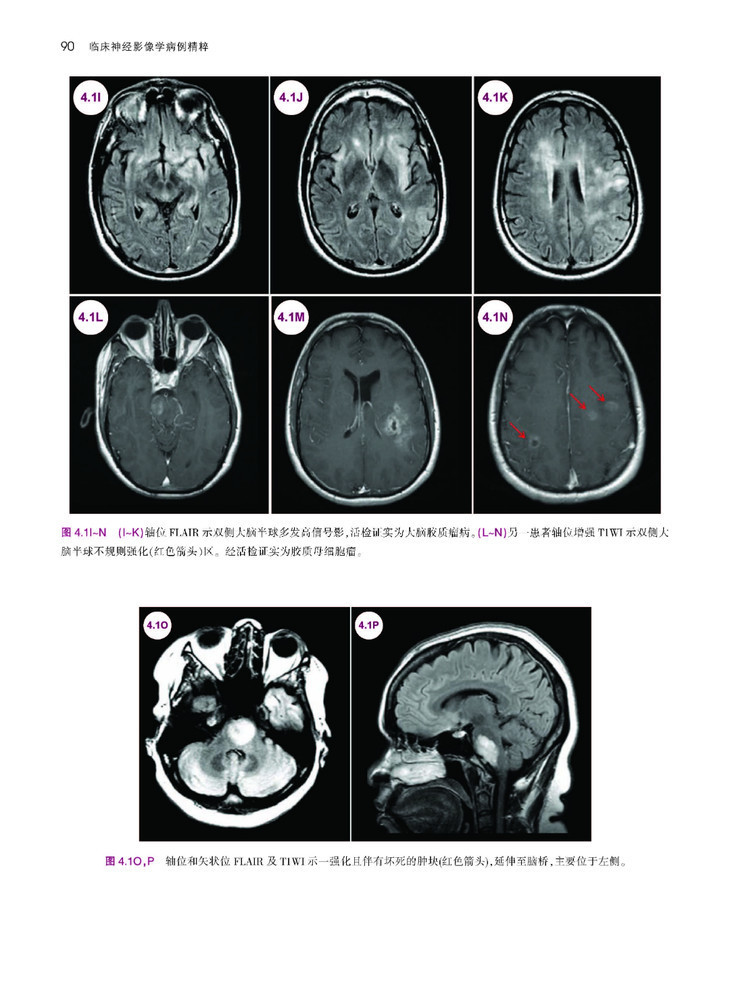

本书是一部极具实用价值的神经系统疾病影像学著作。作者以典型临床病例入手,对疾病发生、影像学和诊治经过进行阐述,并对影像学表现及临床病理机制进行了较为详细的解析,举一反三,扩展并深化了对每一类神经科疾病的认识和理解。本书共列举了超过170个临床病例,涵盖了癫痫、脑血管病、感染、自身免疫疾病、脱髓鞘性疾病、创伤性脑病、神经系统变性疾病和神经系统肿瘤等疾病,内容丰富而全面,且每个病例均资料翔实,条理清楚,行文流畅,图片精美,是神经病学领域难得的一本好书,也是神经科和影像科医师进步与提高不可或缺的专业著作。

本书可以说是一本一体化指南,为神经科医师提供了临床背景下的详细、典型神经影像学病例。作者合理编排本书,通过超过170个病例、1500余幅图像,以影像学表现作为讨论病理生理学、临床表现和疾病诊疗的平台。本书以神经学从业者或学生的角度编写,用易于阅读的形式概述了每种疾病,并配有丰富的图像,从而帮助准确识别和治疗常见、罕见神经疾病。本书共分为15章,涵盖神经病学的主要领域,包括卒中、出血、肿瘤、癫痫、创伤、神经退行性疾病、感染性疾病和儿科病症等。每种疾病均以简要病例和影像学诊断开始,然后是疾病概述、临床表现、影像学表现和诊断、鉴别诊断和治疗。本书通过大量有相似影像表现的病例,以增强神经科医师解读MRI、CT、MRA、血管造影、脑电图、大体和显微神经病理学图像的信心。